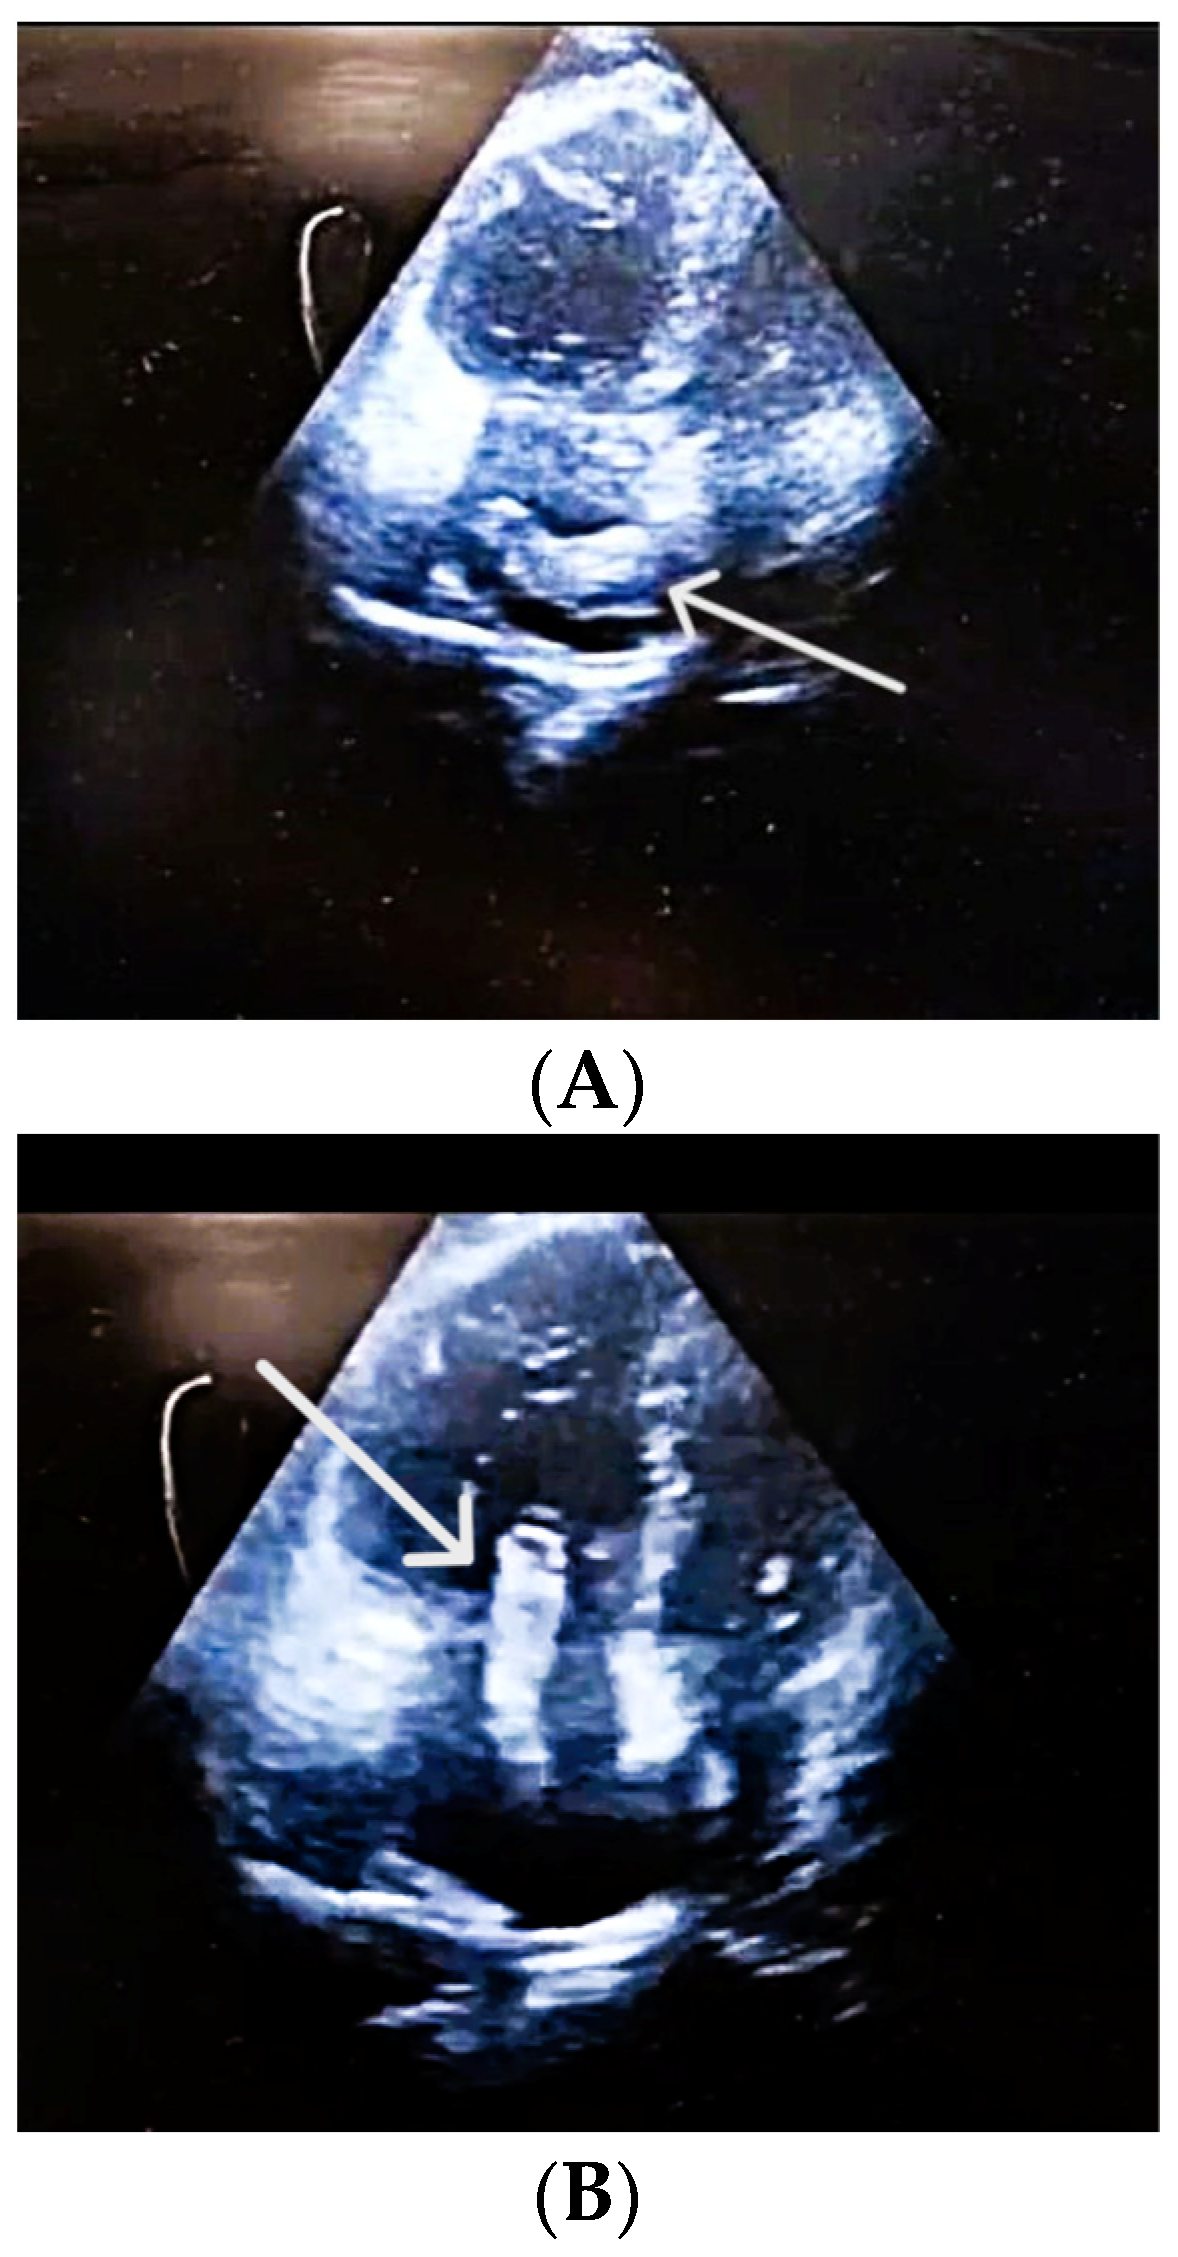

| Proximal DVT end | Lower third of superficial femoral vein | Non-adherent, unstable |

| Thrombus mobility | Free-floating, unstable | High embolization potential |

| Popliteal vein thrombosis | Nearly occlusive thrombus | Consistent with acute DVT |

| DVT extension | Distal into medial posterior tibial vein | Reflects propagation of DVT |